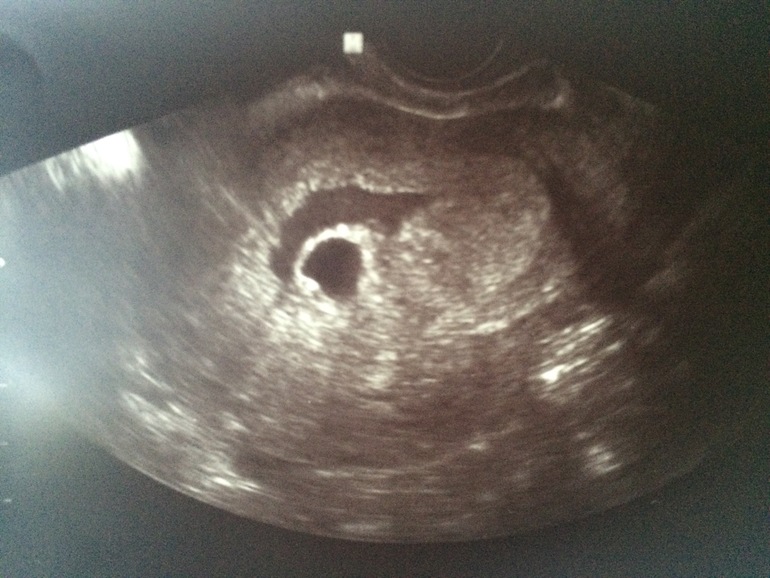

У меня похожая ситуация и срок такой же как у вас! Только мне на узи не написали гематому и значения не придали. А на картинке рядом плодным яйцом прям жидкость. Я почти уверена что это гематома эта,но врачи отмахиваются. Не знаю что делать:( у вас есть фото этой гематомы?